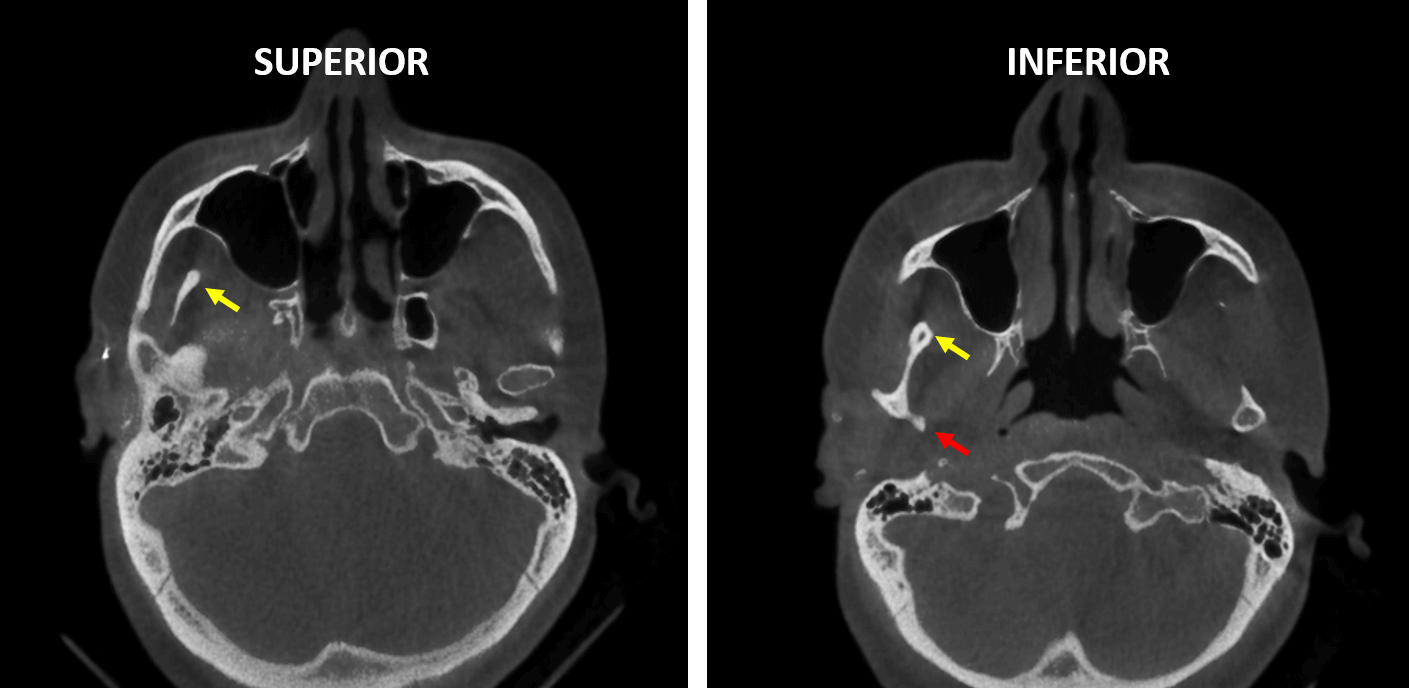

Fig.5

En la reconstrucción tridimensional (Fig.5) se observa la hipoplasia del cóndilo mandibular del lado derecho (flecha roja) y la hiperplasia de la apófisis coronoides del mismo lado (flecha amarilla).